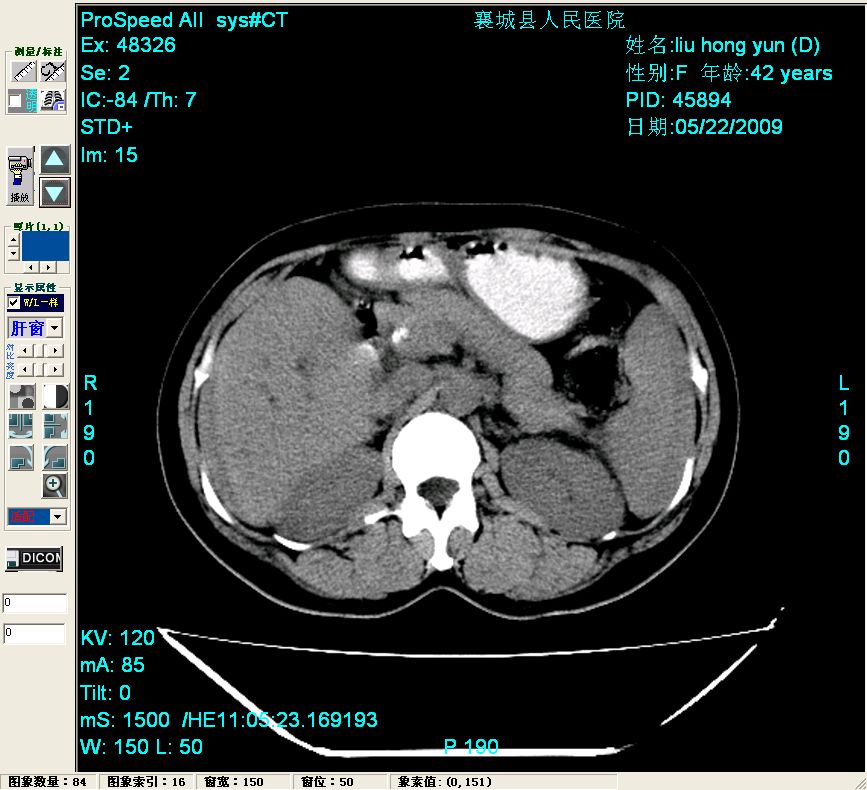

平扫:

平扫左肝外叶体积显著减小,左肝外叶见多房囊性低密度区,左肝实质及右肝前叶浅表实质呈低密度改变,左肝及右肝前叶胆管扩张,脾大

胰头部见结节状高密度影,其前方略可分辨扩强胆部管,平扫到增强始终有,但现在尚难与胃肠造影剂鉴别.

结合病史考虑,1现在引起黄疸体征的原因应该是胆总管胰段结石阻塞,建议局部胃肠造影剂排空后复查.

胆总管末端结石伴肝内胆管扩张合并结石!另:不除外合并胆系感染!

考虑:1、胆道结石伴肝内胆管扩张、积气;胆系感染!2、从平扫、增强片来看,不存在胆管肿瘤征象;3、提介建议:作为影像医师,在做一项检查之前应先熟悉临床医生的目的,象这个病例,检查前就不应喝高密度造影剂,而应充分喝好水就可,要不适得其反,反而较难判断胆总管下段是否有结石。

1)肝内胆管结石,胆总管末端结石伴肝内胆管扩张。2)肝左叶及肝右叶前段增强前后之异常表现,考虑炎性改变,不排除胆管细胞癌。

1)肝内胆管结石,胆总管末端结石伴肝内胆管扩张。2)肝左叶及肝右叶前段增强前后之异常表现,考虑炎性改变,不排除胆管细胞癌。3)脾大。